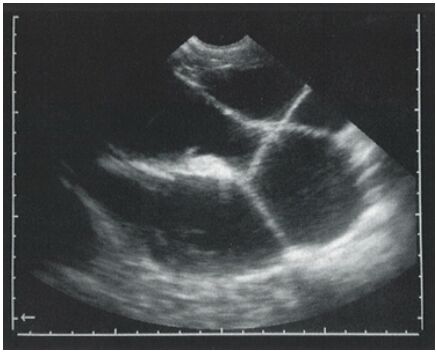

75.以3.5 MHz探頭檢查一頭配種3個月的母山羊,子宮超音波影像顯示如下圖,下列何種治療方法最適當?

(A)注射性腺素釋放激素(GnRH),7天後再注射prostaglandin F 2α (B)置入progesterone陰道塞劑 (C)注射prostaglandin F 2α,12天後再注射一次prostaglandin F 2α (D)注射estradiol,7天後注射prostaglandin F 2α